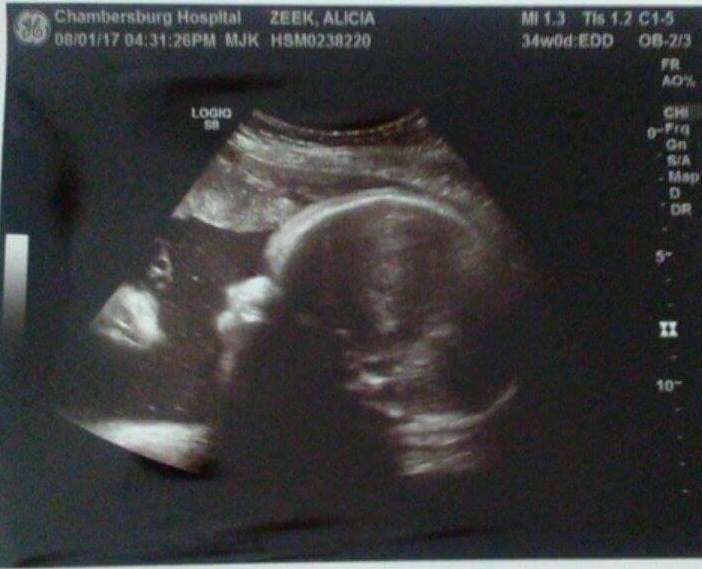

Una coppia americana ha deciso di pubblicare su Facebook l’immagine dell’ecografia a 34 settimane della loro bambina, chiedendo alle persone cosa vedessero.

La madre, Alicia Zeek, ha raccontato su Fox43 di essere rimasta confusa la prima volta che ha visto l’immagine: “Quando ce l’hanno data …ummm, per me, è Gesù. E sembra Gesù” ha esclamato.

Il padre, Zac Smith, invece ha raccontato di aver solo pensato che c’era “un’altra faccia che guardava la figlia!”.

I due genitori hanno spiegato che pur non essendo molto religiosi, entrambi hanno visto un uomo vestito con una corona di spine che guardava la loro bambina.

Il papà ha poi ammesso che l’immagine lo ha reso molto emotivo “quando l’ho vista, mi sono venute lacrime agli occhisono rimasto senza parole, non potevo crederci, non volevo credere a ciò che stavo vedendo“.

Ecco quindi che quando l’ecografista ha detto a questa coppia di genitori che la piccola Briella era sana e felice, i due hanno provato un forte senso di rassicurazione. Poi hanno visto l’ecografia e l’hanno interpretata come una conferma.

Zac dichiara infatti che per loro si tratta di “un segno dall’alto” e dopo aver pubblicato l’immagine su Facebook chiedendo “cosa vedete?” ed aver ricevuto diversi commenti, conferma che secondo loro si tratta di “una benedizione”.